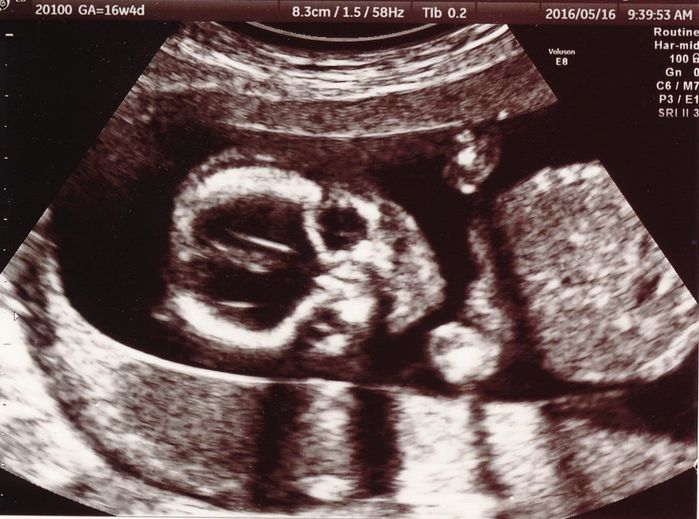

妊娠16週目のエコー写真

赤ちゃんの顔が正面からはっきり写っています。目鼻立ちも分かるので、赤ちゃんの顔を想像していたように思います。あごの近くにある2つの白丸は小さな両手です。